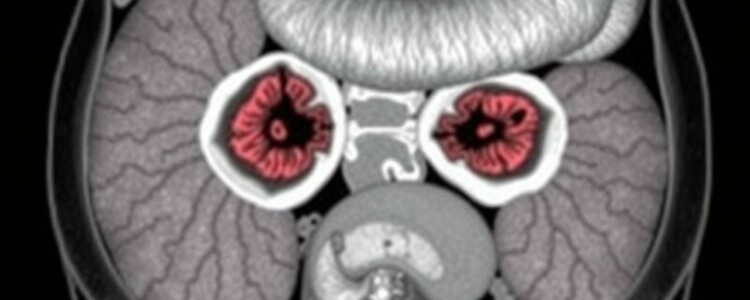

En la práctica habitual, el flujo diagnóstico suele ser: apendicectomía → informe histopatológico que identifica el tumor → decisión sobre tratamiento adicional o seguimiento → en caso necesario, estudios de imagen para descartar metástasis. Para evaluar la extensión y la presencia de enfermedad a distancia se recurren a técnicas como la tomografía computarizada (TC), la resonancia magnética (RM) y las imágenes funcionales específicas para tumores neuroendocrinos, como la PET con Ga-68 DOTATATE o el gammagrama con Octreoscan.

| RM hepática | Detección más sensible de lesiones hepáticas | Si hay sospecha de metástasis hepáticas |

| Gammagrafía Octreoscan / PET Ga-68 DOTATATE | Detecta receptores de somatostatina; útil para estadiaje y tratamiento dirigido | En enfermedad avanzada o metastásica; antes de PRRT |